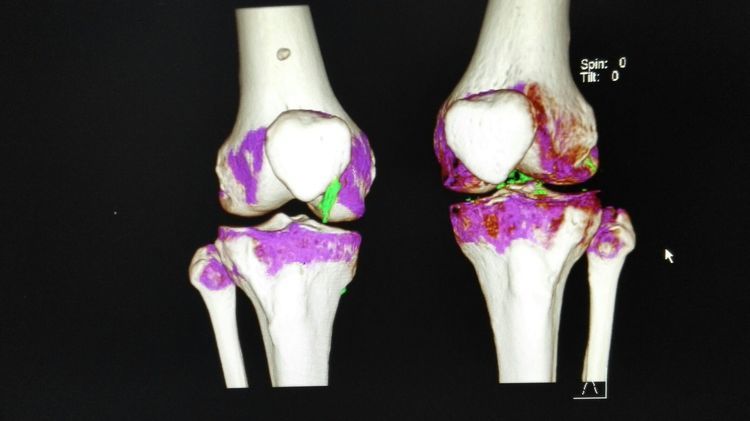

500余例关节镜手术的感悟--251运动医学现状

关节镜手术是一种微创手术,它以微切口,创伤小,恢复快,效果好为特点,逐渐被越来越多的人接受。在治疗关节疾病方面有着绝对的优势,而且越来越多的非关节疾病也开始使用关节镜处理,如:皮下肿物,弹响髋,跟腱延长等都可以利用关节镜处理。随着关节镜技术的日益成熟与发展,它独特的优势必将成为成千上万患者的福音。下面展示一下手术图片:

镜下手术图片,展示人体关节镜下情况:

骨科中心近两年共收治关节镜手术病人500余人,本人在近半年共收治关节疾病患者70余人,包括肩关节脱位及盂唇损伤、半月板损伤、交叉韧带损伤、叉韧带止点撕脱、髌骨脱位、色素性滑膜炎、关节游离体、老年骨性关节炎、踝关节外侧副韧带损伤伴距骨软骨损伤等。均通过关节镜或辅助关节镜手术治疗,短期内随访效果好,总体满意率在95%以上。

特别值的一提的是关节镜清理和韧带松解辅助关节腔注射治疗老年膝关节骨性关节炎效果明显,术后患者膝关节疼痛明显减轻,提高了生活质量,延缓了疾病的进展。当然术前查体及适应症的选择十分重要,患者的信任及配合,术前教育和术后康复指导也都是十分重要的。远期效果我会把随访结果分享给大家,希望大家共同关注老年膝关节骨性关节病!